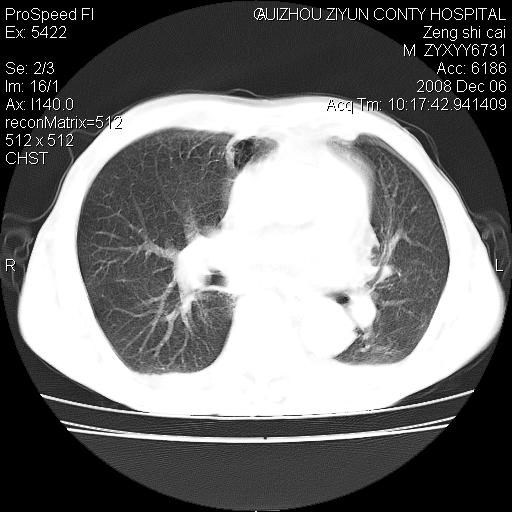

标题: CT16961:M、71岁,咳嗽半年,无血痰;胸片示右肺占位。 [打印本页]

标题: CT16961:M、71岁,咳嗽半年,无血痰;胸片示右肺占位。

1)考虑右肺上叶纵隔型肺癌伴纵隔淋巴结转移。2)心包积液,双侧胸腔积液。

右肺上叶纵隔型肺癌伴纵隔淋巴结转移。心包积液,双侧胸腔积液。